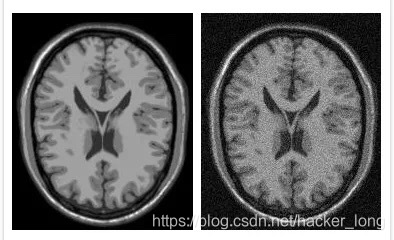

模拟图像和数字图像的对比,大家可以看看。